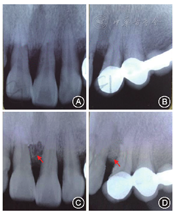

粘接固定。牙周手术后3个月复查(图4),X线片显示

近中植骨区有高密度影形成(图5)。拆除

术前;B:

术前;C:

术后;D:

术后

术后(3)正畸:2012年7月至2013年11月,上下颌牙齿分别开始正畸加力(图6,图7),期间每3个月进行一次牙周维护。